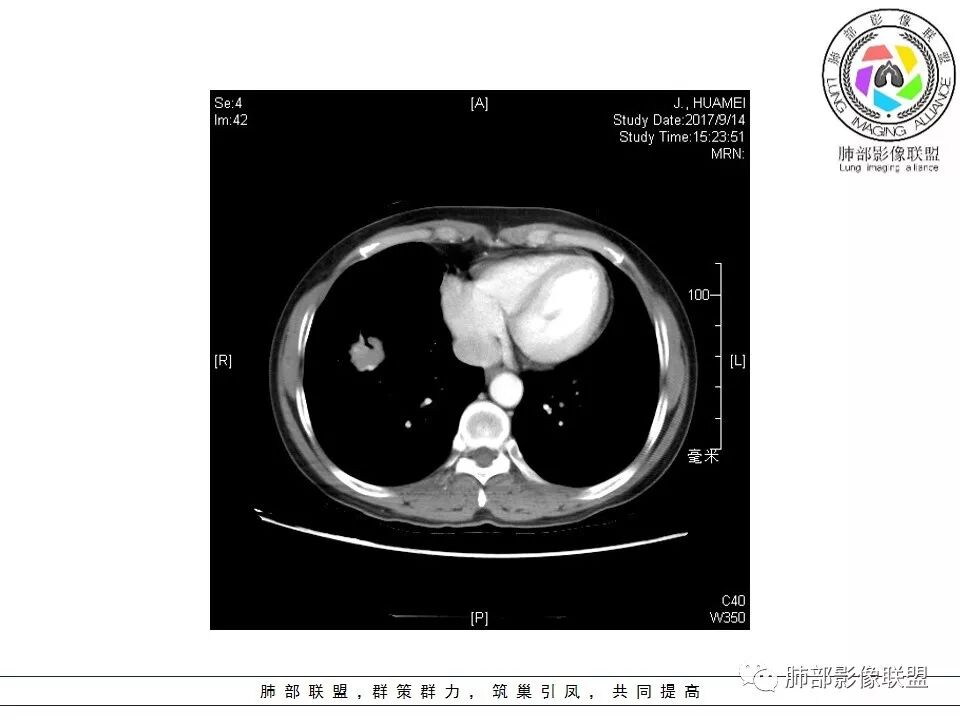

中年女性,右肺下叶前基底段肿块,轻度分叶,有棘样突出,充气支气管征穿行并形成脐凹征。增强扫描中度强化,内见血管影,血管壁毛糙,考虑恶性,腺癌?小细胞肺癌?

晨读,右肺下叶前基底段实性结节,边缘膨隆,可见多发浅分叶,结节内密度均匀,增强后呈轻度均匀强化,血管穿行走形自然,首先考虑恶性肿瘤,内有支气管穿行,淋巴瘤可能大,腺癌待排。

这个病灶边缘还是有一点点恶性征象,有分叶,似乎有点地方还有一些小毛刺样感觉

部分区域整体以膨隆为主,部分区域稍收缩

内部支气管走形非常自然,达远端稍扩张;内部血管穿行也非常自然

内部密度比较均匀,我们一般来说,首先良性肿瘤不支持,因为它里面的血管走形太自然了;然后就是炎性病变跟恶性肿瘤,但是它的边缘膨隆比较厉害,有些地方还毛刺,不是很清楚,倾向一个恶性病变

病灶分布:因为肺内淋巴瘤主要侵犯对象是肺间质和支气管黏膜下组织,病灶主要位于在沿支气管血管束分布、肺间质及胸膜下,病灶可跨叶分布

病灶的密度:密度均匀,部分病灶内可见空洞及气液平,轻中度均匀强化

病灶的边缘:有膨隆,浅分叶,也有平直、收缩,平直收缩是因为肿瘤组织浸润致肺泡塌陷及周围纤维组织增生,牵拉正常的肺组织向病灶中心形成聚拢状改变,似呈“炎性”改变。

支气管充气征伴或不伴支气管扩张:肿瘤细胞沿肺间质及支气管黏膜下组织浸润,支气管管壁未见明显破坏,管腔内未见肿瘤细胞充填,呈现充气支气管征;充气支气管走行自然,无扭曲、僵硬,内壁管腔光滑,支气管管壁见增厚并常有管腔的扩张,含气支气管可呈串珠样不均匀扩张,扩张明显处呈空腔样或皂泡样的囊状含气影;支气管扩张目前有两种意见:一是由于肿瘤组织起源于肺间质,肿瘤沿或跨越脏器解剖结构生长,原有解剖结构残留,周围增生的纤维结缔组织牵拉导致支气管扩张;二肿瘤侵犯支气管粘膜下植物神经丛致平滑肌张力丧失;而这类支气管扩张在肿瘤治疗后有时可消失。

血管造影征:肿瘤组织浸润引起间质增厚、肺泡壁破坏、肺泡腔充填,而周围充盈血管走行自然,未受肿瘤侵犯。